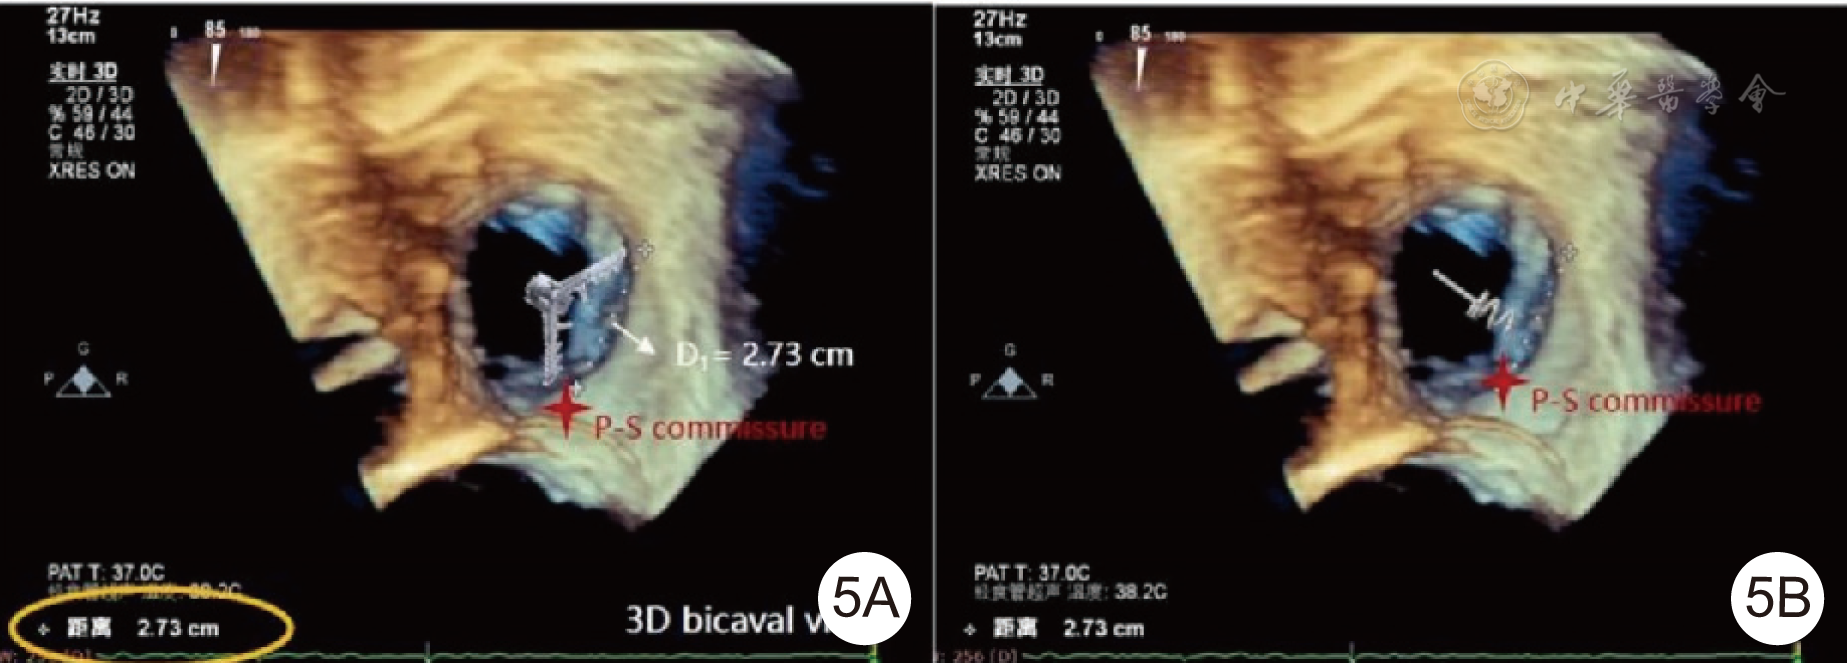

图3 术前 TEE 评估[3A为食管中段四腔心切面,显示双心房明显增大,三尖瓣关闭见缝隙;3B为根据食管中段聚焦三尖瓣环全容积显像定量评估三尖瓣环左右径、前后径、面积及周长;3C为三尖瓣三维外科视野,清晰显示前叶、后叶及隔叶,并见巨大关闭缝隙;3D为食管中段四腔心切面,彩色多普勒显示重度 TR;3E为食管中段 X-Plane 双切面(食管中段大血管短轴切面及食管中段反四腔心切面),彩色多普勒显示重度 TR;3F为三尖瓣三维外科视野,彩色多普勒显示三尖瓣中央区重度TR]注:TEE为经食管超声心动图,TR为三尖瓣反流